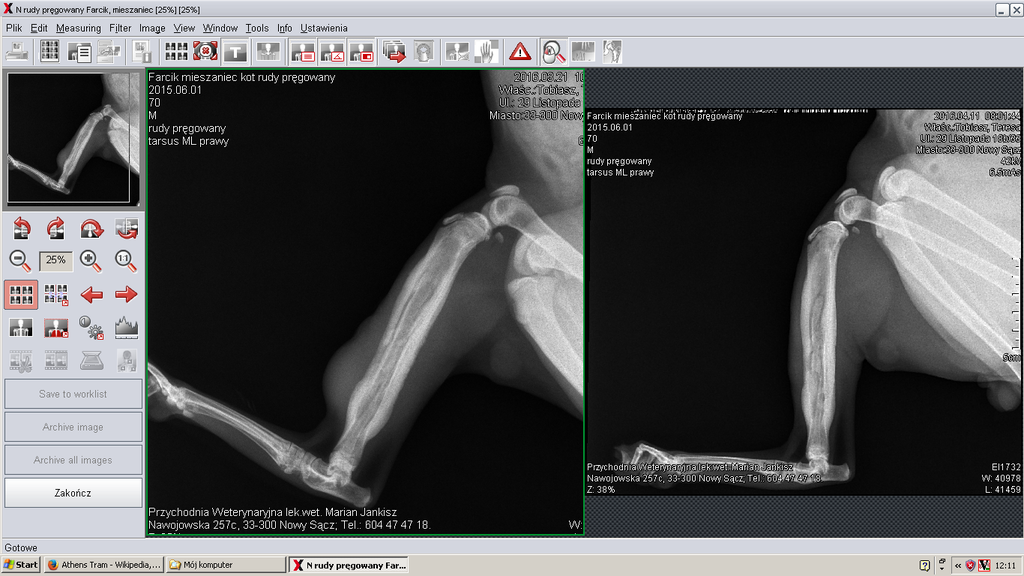

Teresa już 2 razy próbowała wysłać zdjęcia kości z pierwszego i drugiego prześwietlenia, ale nie potrafi ich otworzyć, bo są jakoś dziwnie zapisane. Jeszcze ma dziś spróbować. Bardzo bym chciała je Wam pokazać...

Teresa już 2 razy próbowała wysłać zdjęcia kości z pierwszego i drugiego prześwietlenia, ale nie potrafi ich otworzyć, bo są jakoś dziwnie zapisane. Jeszcze ma dziś spróbować. Bardzo bym chciała je Wam pokazać...

Ja się na opisie rtg nie znam

ale nózia śliczna <serce>

ale nózia śliczna <serce>